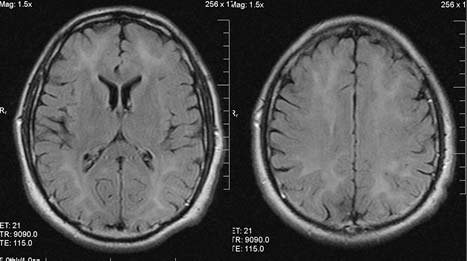

Повторное МРТ-исследование головного мозга (рис. 2): «На Т2-изображениях видно гиперинтенсивное перивентрикулярное белое вещество с поражением лобных и затылочных долей».

Рис. 2. Магнитно-резонансная томограмма головного мозга пациента Н. на 15-й день пребывания в неврологическом отделении

«Светлый промежуток» с отсроченностью клинических проявлений обусловлен, с одной стороны, определёнными сроками, которые необходимы для формирования иммунного ответа (поздний иммунный ответ формируется через 96 ч и более), с другой стороны — постепенно нарастающим в результате иммунного повреждения поражением нервной ткани. Данное предположение подтверждается результатами нейровизуализации в динамике — у больного по данным МРТ, сделанной на 2-й день после первых симптомов ОПЛ, уже определялись очаги демиелинизации (см. рис. 1), площадь их вместе с нарастанием клинических симптомов увеличивалась (см. рис. 2, 3).